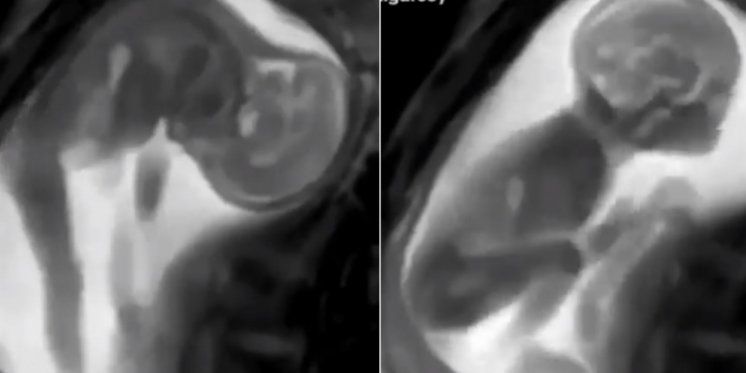

Nerođena beba proteže se, isteže ručice i nožice, katkada reagira na vanjske zvukove ili majčine osjećaje. Kako to otprilike izgleda može se vidjeti na snimci magnetne rezonance, video koji je objavio engleski Independent na svojim stranicama zorno pokazuje kako izgleda bebino kretanje unutar maternice.

Snimka je zanimljiva pogotovo budućim majkama jer daje divan pogled na to kako njihova beba provodi vrijeme u trbuhu.